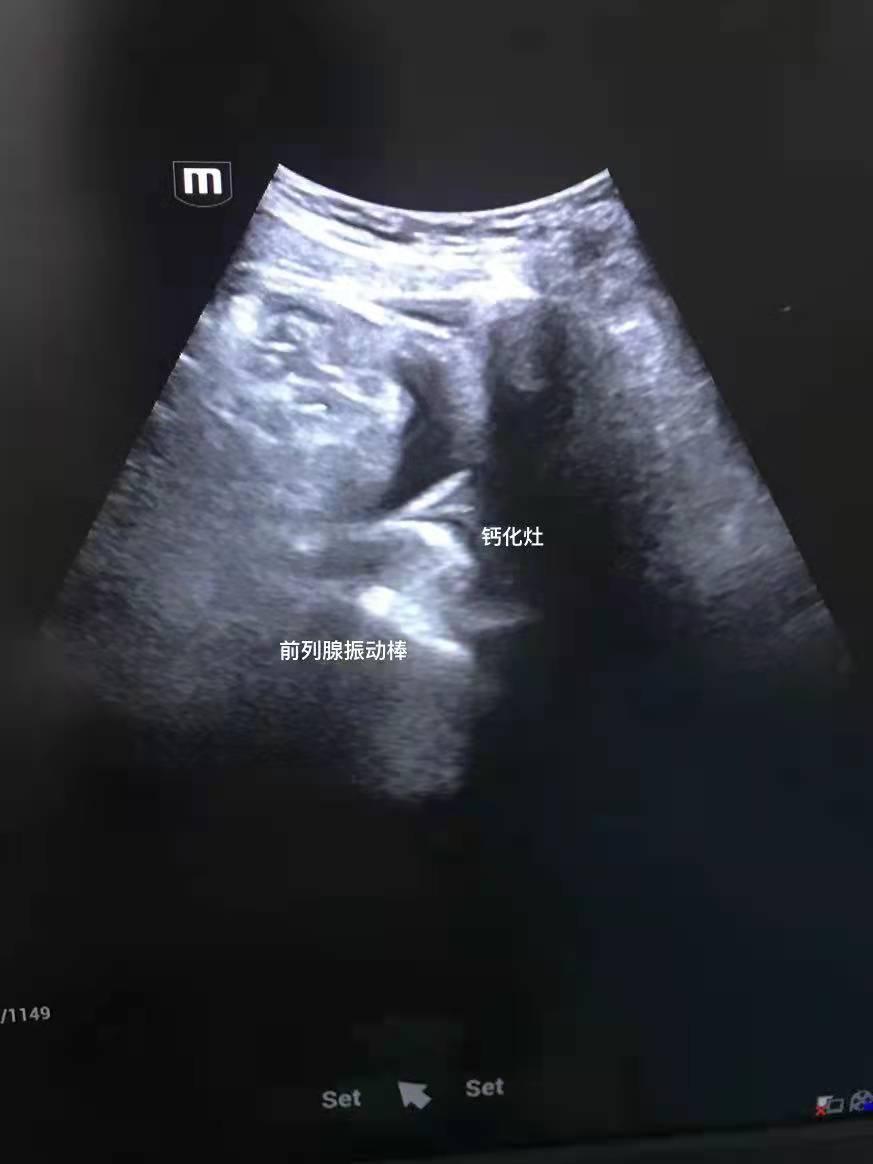

病灶点定位方法(b超加理疗棒法):做腹部b超,理疗棒插入肛门,在b超屏幕上可同时能看到理疗棒和钙化点(或回声不均匀的点(堵塞),或无回声点(囊肿)),这些点就是病灶点,移动理疗棒,让病灶点和理疗棒重合,用理疗棒反复顶病灶点,观察病灶点是否随着棒子动,最后记住这个位置的深度(用记号笔在理疗棒上标记)和角度(记住理疗棒偏几点钟方向),有的患者不止一个病灶点,需要依次定位,理疗时只做这些病灶点就行,有的患者担心出口堵塞,可以理疗一下中央沟位置。

病灶点定位方法(痛点法):先找到病灶点,理疗棒先插入一点,左右扫一下,再插入一点,再左右扫一下,把整个前列腺的后叶和侧叶都扫一遍,找到最疼最不舒服的点,病灶点就在这个点的附近,这样就知道患者的病灶点大概位置了,用手拿着理疗棒,用一定的力度,用理疗棒顶住这个点不要再动了(痛点一旦跑偏就不容易再次找到了),然后就打开理疗器开始振动,振动力度调到患者能承受的力。